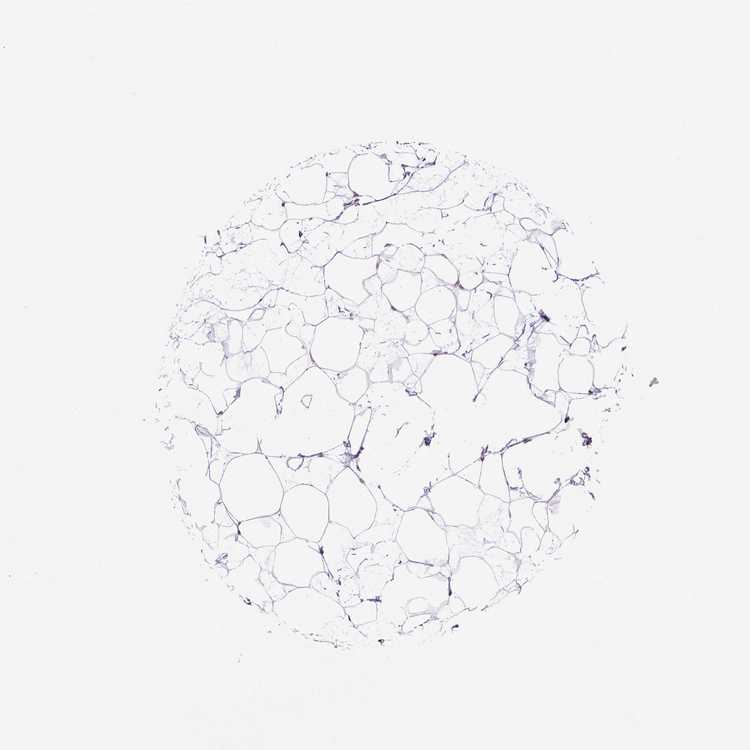

BREAST - Antibody stainingi

Antibody staining in the annotated cell types in the current human tissue is reported as not detected, low, medium, or high, based on conventional immunohistochemistry profiling in selected tissues. This score is based on the combination of the staining intensity and fraction of stained cells.

Each image is clickable and will lead to virtual microscopy that enables deeper exploration of all samples and also displays staining intensity scores, fraction scores and subcellular localization as well as patient and tissue information for each sample.

Antibody HPA032095Antibody HPA032096

Adipocytes LowNot detected

Glandular cells Not detectedLow

Myoepithelial cells Not detectedNot detected